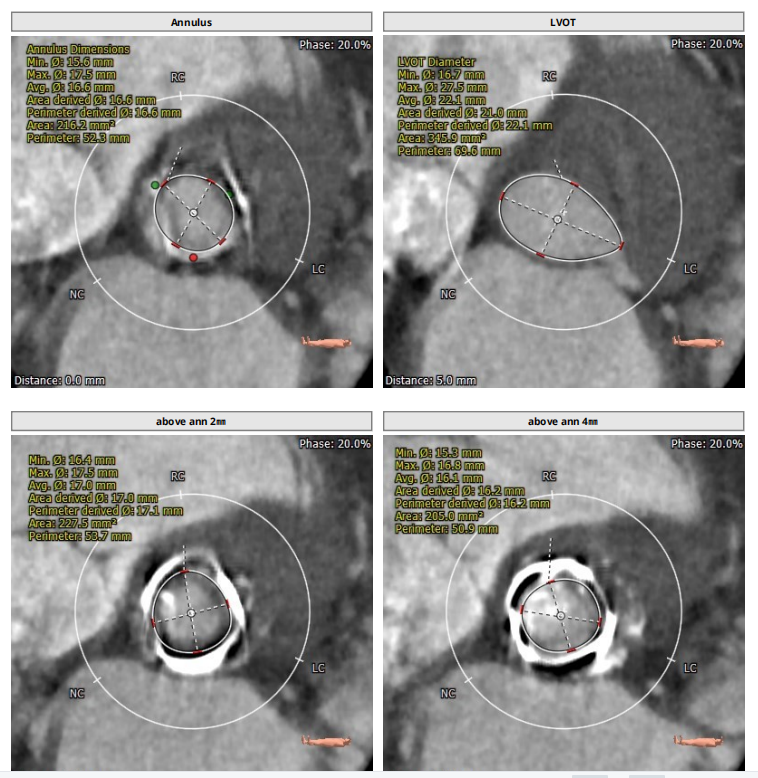

术前CT评估报告

2、主动脉瓣置换术后,瓣口面积极小,导致瓣膜无法稳定锚定,需要术中时刻观察调整。

3、选用18mm球囊预扩、L23号VenusA-Valve瓣膜、采用VenusA-Plus输送系统确保瓣膜的精确释放,释放过程中灵活调整瓣膜位置,密切关注瓣膜形态,瓣膜释放后结合造影和超声情况,决定是否后扩。

术后造影及经食道超声探查未见瓣周漏,人工瓣膜无明显返流,跨瓣压差术前100mmHg,术后降为10mmHg,术中及术后未出现相关并发症,手术圆满完成。

3、释放瓣膜时需要时刻观察瓣膜位置和瓣膜形态变化,术者结合瓣膜释放后造影和超声情况决定使用18mm球囊进行后扩,情况得到即刻改善。